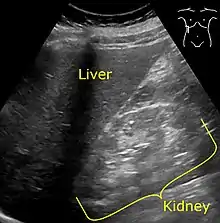

It is recommended that diabetics have their albumin levels checked annually, beginning immediately after a diagnosis of type 2 diabetes and five years after a diagnosis of type 1 diabetes.[25][28] Medical imaging of the kidneys, generally by ultrasonography, is recommended as part of a differential diagnosis if there is suspicion of urinary tract obstruction, urinary tract infection, kidney stones or polycystic kidney disease.[29] Conformation kidney biopsy should only be performed if non-diabetic kidney disease is suspected.